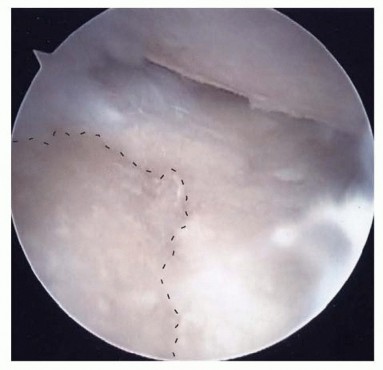

With the joint exposed, the precise location of the impingement is visually confirmed by taking the wrist through a range of motion, particularly radial deviation and extension. The osteotomy is then performed. A micro-sagittal saw or a sharp, thin osteotome is utilized. The cut is initiated on the lateral extra-articular cortex, no more than 3 to 4 millimeters proximal to the tip of the styloid. The blade is directed obliquely, aiming distally and ulnarly to exit precisely at the junction of the styloid and the scaphoid fossa. During the osteotomy, a Freer elevator or a small Hohmann retractor is placed intra-articularly to protect the articular cartilage of the scaphoid from iatrogenic injury.

Image

Following the initial resection, the bony fragment is excised, and the osteotomy site is meticulously smoothed using a rongeur or a high-speed burr to eliminate any sharp cortical edges that could abrade the joint capsule or adjacent tendons. Copious irrigation is employed to remove all bone debris, which could otherwise serve as a nidus for heterotopic ossification or third-body wear. Fluoroscopic evaluation in both AP and lateral planes is mandatory at this juncture to confirm adequate resection and verify that the 3-4mm safe zone has not been violated. The wrist is taken through a full, dynamic range of motion under live fluoroscopy to ensure that impingement has been completely eradicated.